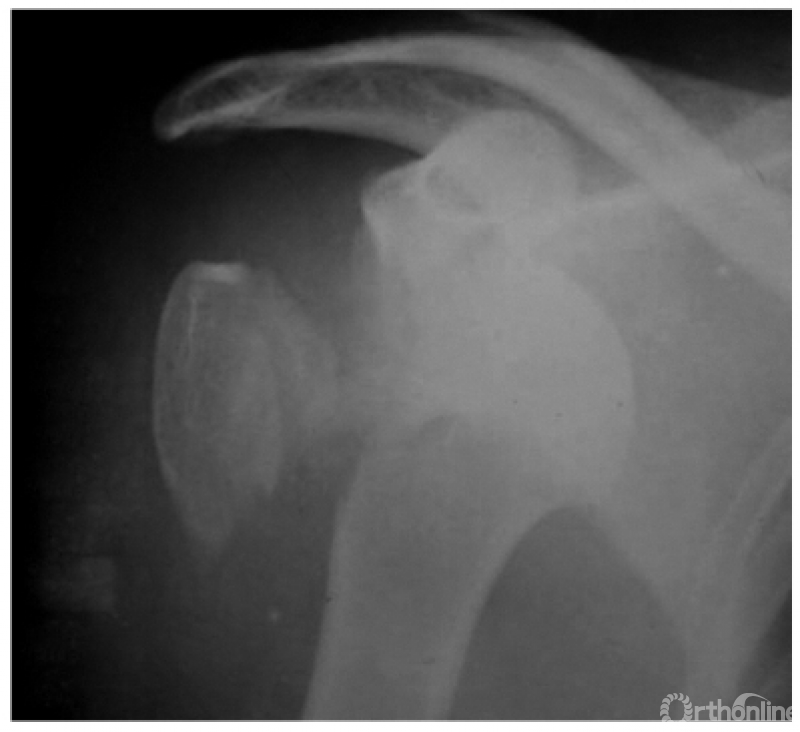

此外,由于脱位后上臂外旋受限,因此即使在最大外旋位拍片时仍不能显示出肱骨颈及大结节的轮廓。例:肱骨头离开关节盂而向后外上方(肩峰之下)移位且内旋,致肱骨头与肱骨干在一直线上,招致肩肱曲线不流畅,肱骨头关节面与盂前缘距离大于6mm并小结节骨折(如下图)。